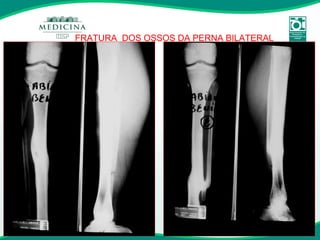

FRATURA  DOS OSSOS DA PERNA BILATERAL